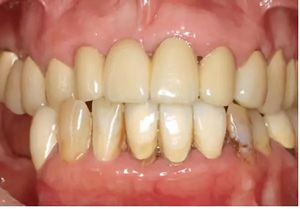

圖2-圖6:2013 年10 月15 日口內(nèi)狀況。

口外檢查未發(fā)現(xiàn)異常。牙齒和牙周狀態(tài)如圖1 和2-6所示??傮w來(lái)說(shuō),已有的修復(fù)體已不完善。第一次就診時(shí),檢查發(fā)現(xiàn)17、15、11、36、45 和46 號(hào)牙齒已缺失。16、14、12、27、37 和35 號(hào)牙齒已做過(guò)根管治療。所有剩余的牙齒牙髓活力測(cè)試均正常,叩診檢查未見(jiàn)異常。橋基牙37 已發(fā)生大面積的繼發(fā)齲,33 號(hào)牙齒齲壞和43 號(hào)牙齒繼發(fā)齲。16 和14 號(hào)牙齒根管充填不足且有根尖周炎。35 號(hào)牙齒的根管充填似乎是邊緣封閉、無(wú)氣泡,但也欠充。所有需要保留的牙齒的平均牙周附著喪失為5-6mm(最大9mm),探診深度(ST)為4-5mm(最大8mm)。27 號(hào)牙齒單獨(dú)的探診深度已達(dá)15mm。牙齦緣普遍松軟,下頜前牙舌側(cè)區(qū)域附著堅(jiān)硬的菌斑。整個(gè)邊緣牙齦發(fā)生炎癥性改變,特別是腭側(cè)區(qū)域。